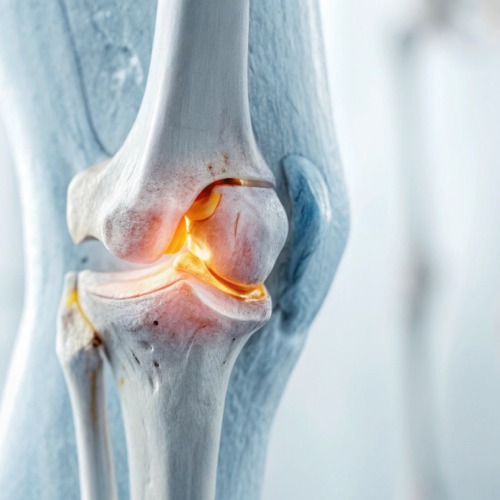

Artroscopia della Spalla e del Ginocchio

L’artroscopia della spalla e del ginocchio è una tecnica chirurgica minimamente invasiva che consente al Dott. Edoardo Cristalli di trattare con precisione diverse problematiche articolari. Questa metodica è particolarmente indicata per risolvere lesioni della cartilagine, lesioni ai legamenti o alla cuffia dei rotatori della spalla e danni alle articolazioni del ginocchio, come le rotture del menisco o dei legamenti crociati. Grazie a piccoli incisions e l’uso di strumenti specializzati, l’artroscopia permette un recupero rapido, con un minor dolore post-operatorio e un ritorno veloce alle normali attività.